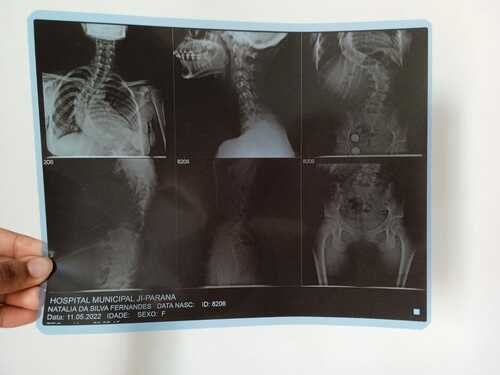

Olá, me chamo Natália da Silva Fernandes, tenho 21 anos, moro na cidade de Ji-Paraná, no estado de Rondônia. Fui diagnosticada com escoliose e venho na busca de um tratamento pelo SUS há um tempo, mas não obtive retorno até o presente momento. Passei por algumas consultas com ortopedistas do SUS, peguei encaminhamentos para passar com um neorocirurgiao e depois de um longo período de espera, consegui uma consulta com um neorocirurgiao do SUS, quando ele viu meu estado de saúde ele disse q a única solução é fazer a cirurgia, como na cidade não tem estrutura para realizar a cirurgia através do SUS, peguei mais um encaminhamento para consultar pela segunda vez por outro neurocirugiao, mas na cidade de Porto Velho, e nisso fiquei no aguardo desse agendamento mas até o momento nenhum retorno do SUS, ou seja, nenhum pedido de agendamento de cirurgia, apenas consultas, é um processo burocrático conseguir uma cirurgia pelo SUS, pois tem uma lista de pacientes na espera por vaga. Devido à demora do SUS , recorri a um neurocirurgião particular e o diagnóstico que recebi foi o mesmo, necessito fazer a cirurgia com urgência.Atualmente, me encontro num quadro doloroso, minha escoliose está com 86° de encurvatura, sinto dores constantes, tenho dificuldade em andar e às vezes dificuldade em respirar, porque são dores muito fortes. Para dormir, é uma luta constante para achar uma posição que dê menos desconforto . Diante de todo esse processo doloroso, e todo o tempo que venho recorrendo ao SUS e não obtendo uma solução favorável, a preocupação aumenta cada dia, pois não tenho condições de custear nem a cirurgia, nem o tratamento pós-cirúrgico. Foi então que surgiu a solução de fazer a vaquinha. A cirurgia fica em média de 250 mil reais com o tratamento pós-cirúrgico. Deixo na descrição os laudos e exames que venho realizando como transparência da minha situação.Toda ajuda é bem-vinda!Ajude-me compartilhando em suas redes sociais. Deixarei minha rede social para entrarem em contato comigo para mais informações: @_fe3_n47ou acesse o link abaixo e vá direto ao meu perfil.https://www.instagram.com/_fe3_n47?igsh=MXA1bDEzNW53YzZ5NA==